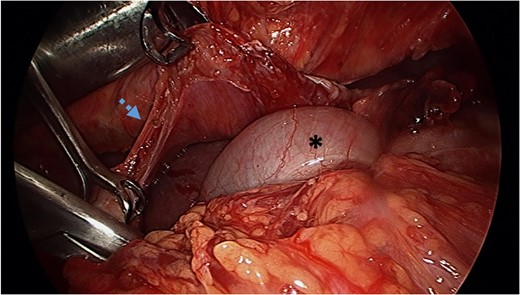

Reduction of transverse colon into abdominal cavity. The spleen is visible adjacent to the transverse colon. Black asterisk (*) indicates a loop of transverse colon. Blue broken arrow indicates the diaphragmatic defect that was extended to successfully reduce the colon.